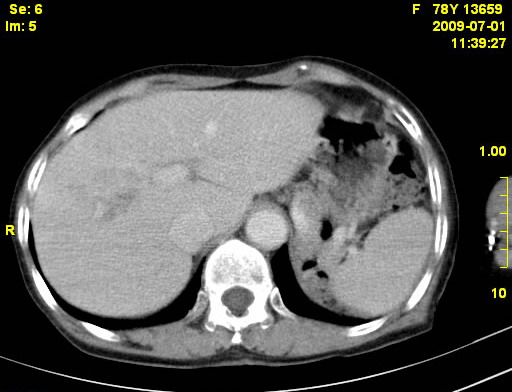

以下是引用zjzjr在2009-7-3 11:02:00的发言:[br]动脉期不均匀强化,门脉期及延迟期强化明显,肝门部见肿大淋巴结影,肝内胆管扩张.考虑肝右叶前段胆管细胞癌伴肝门淋巴结转移,胆内胆管扩张.慢性胆囊炎.

以下是引用dsl555在2009-7-4 10:59:00的发言:[br]考虑肝右叶前段胆管细胞癌伴肝门淋巴结转移,胆内胆管扩张.慢性胆囊炎. [br][br]支持。